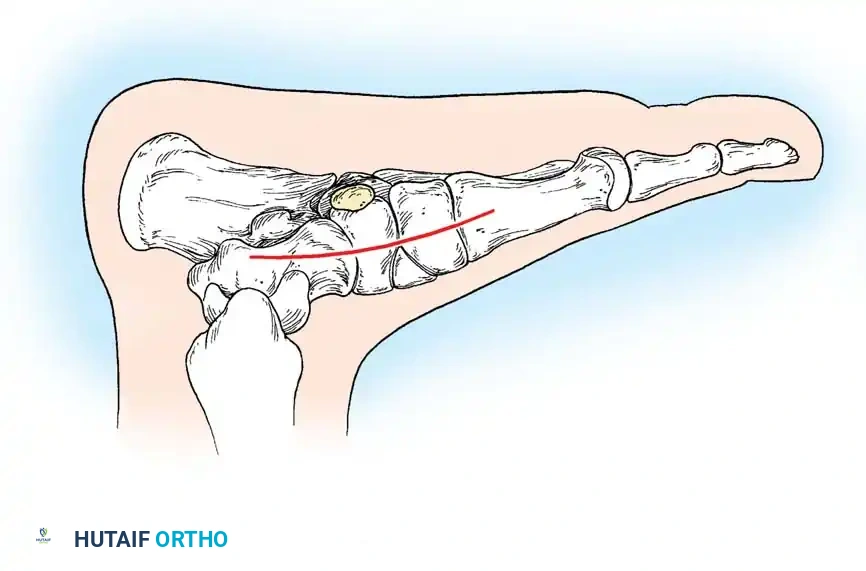

لفهم طبيعة القدم المسطحة الصلبة، يجب أولاً إلقاء نظرة مبسطة على تشريح القدم. تتكون القدم البشرية من مجموعة معقدة من العظام، المفاصل، الأربطة، والأوتار التي تعمل معاً بتناغم لتشكيل "قوس القدم" الطولي. هذا القوس يعمل كممتص للصدمات ويساعد في توزيع وزن الجسم أثناء المشي والركض.

في الحالة الطبيعية، تتحرك عظام الجزء الخلفي والأوسط من القدم (مثل عظمة الكاحل، وعظمة العقب، والعظمة الزورقية) بحرية لتتكيف مع الأسطح المختلفة. ولكن في حالة القدم المسطحة الصلبة، يحدث تقييد شديد أو انعدام كامل لهذه الحركة، مما يؤدي إلى تصلب القدم وفقدان القوس الطبيعي بشكل دائم، سواء أثناء الوقوف أو الجلوس.

* التحام العقب والزورقي (Calcaneonavicular Coalition): جسر يربط بين عظمة الكعب (العقب) والعظمة الزورقية.

* التحام الكاحل والعقب (Talocalcaneal Coalition): جسر يربط بين عظمة الكاحل وعظمة الكعب، وغالباً ما يحدث في المفصل الأوسط.